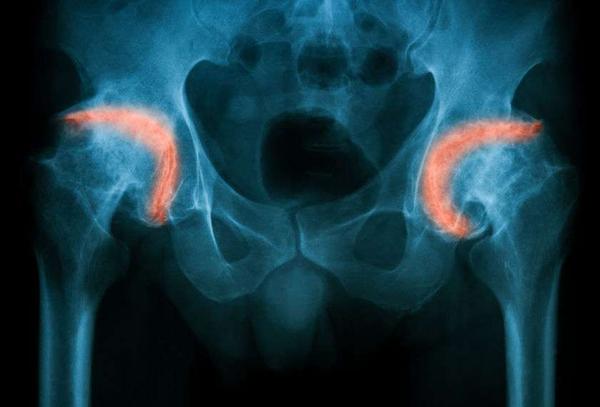

殊不知 , 对于老年人而言 , 一次意外骨折、特别是股骨颈骨折之后 , 可能就意味着死神即将降临了 。

要知道 , 髋部这个位置十分特殊 , 它连接了人体大腿和臀部 , 可以说是人体上半身的“承重墙” 。

股骨则是支撑人体的大腿骨 , 它为全身骨骼最为粗壮的一根 , 只有在髋部和股骨的配合之下 , 人体才能正常站立和行走 。

但是 , 老年人却不相同 , 之所以老年人髋部骨折病发率较高 , 是因为人到了老年之后 , 身体素质变得越来越差、骨质流失严重 , 绝大部分老年人都合并了骨质疏松问题 , 且肌肉也在逐渐萎缩 , 变得越来越脆弱 , 骨骼就如同酥脆的饼干 , 一个小小的跌倒就可能会造成髋部骨折;

而一旦这面“承重墙”倒塌 , 就意味着患者无法站立和正常行走 , 甚至是连坐起来、翻身都十分困难 。